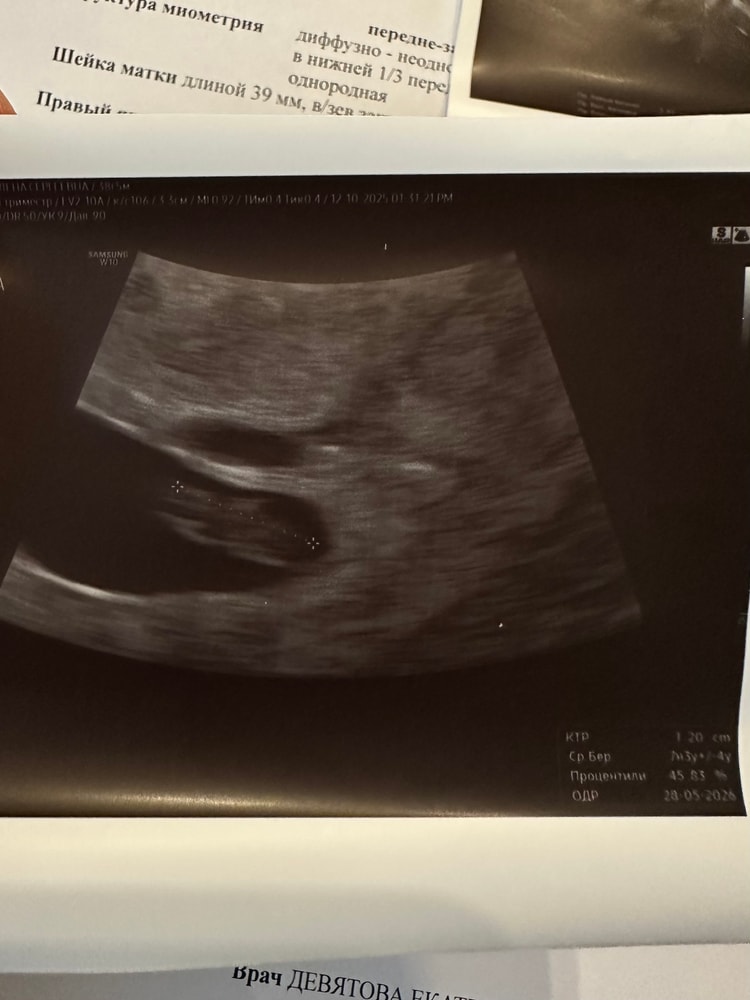

Как только вставила датчик, я сразу увидела на экране сердцебиение и моментально отпустило🙏🏻 Эмбрион живой. ЧСС отличное - 164 уд.в мин., ритм правильный (послушала)❤️ Хорион (зачатки плаценты) 7 мм, соответствует сроку. КТР 12 мм (высоконький кто-то видимо будет😁), соответствует сроку.

По нижнему краю ПЯ небольшая ретрохориальная гематома в 1 см. Возможно потому были выделения, матка растет-лопнул сосудик + аденомиоз, кс, полипэктомии в анамнезе. До 3 см гематома не представляет опасности для плода. Сказала, что должна рассосаться, наблюдать, желательно через 2 недели повторить узи (там уже как раз скрининг +/-).

На фотокарточке малыш🫶🏼 и над ПЯ темное овальное включение - тот самый синячок😒